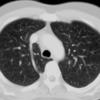

Aortic nipple

Ex 1 CT

Date: 03/23/2004

Views: 5232